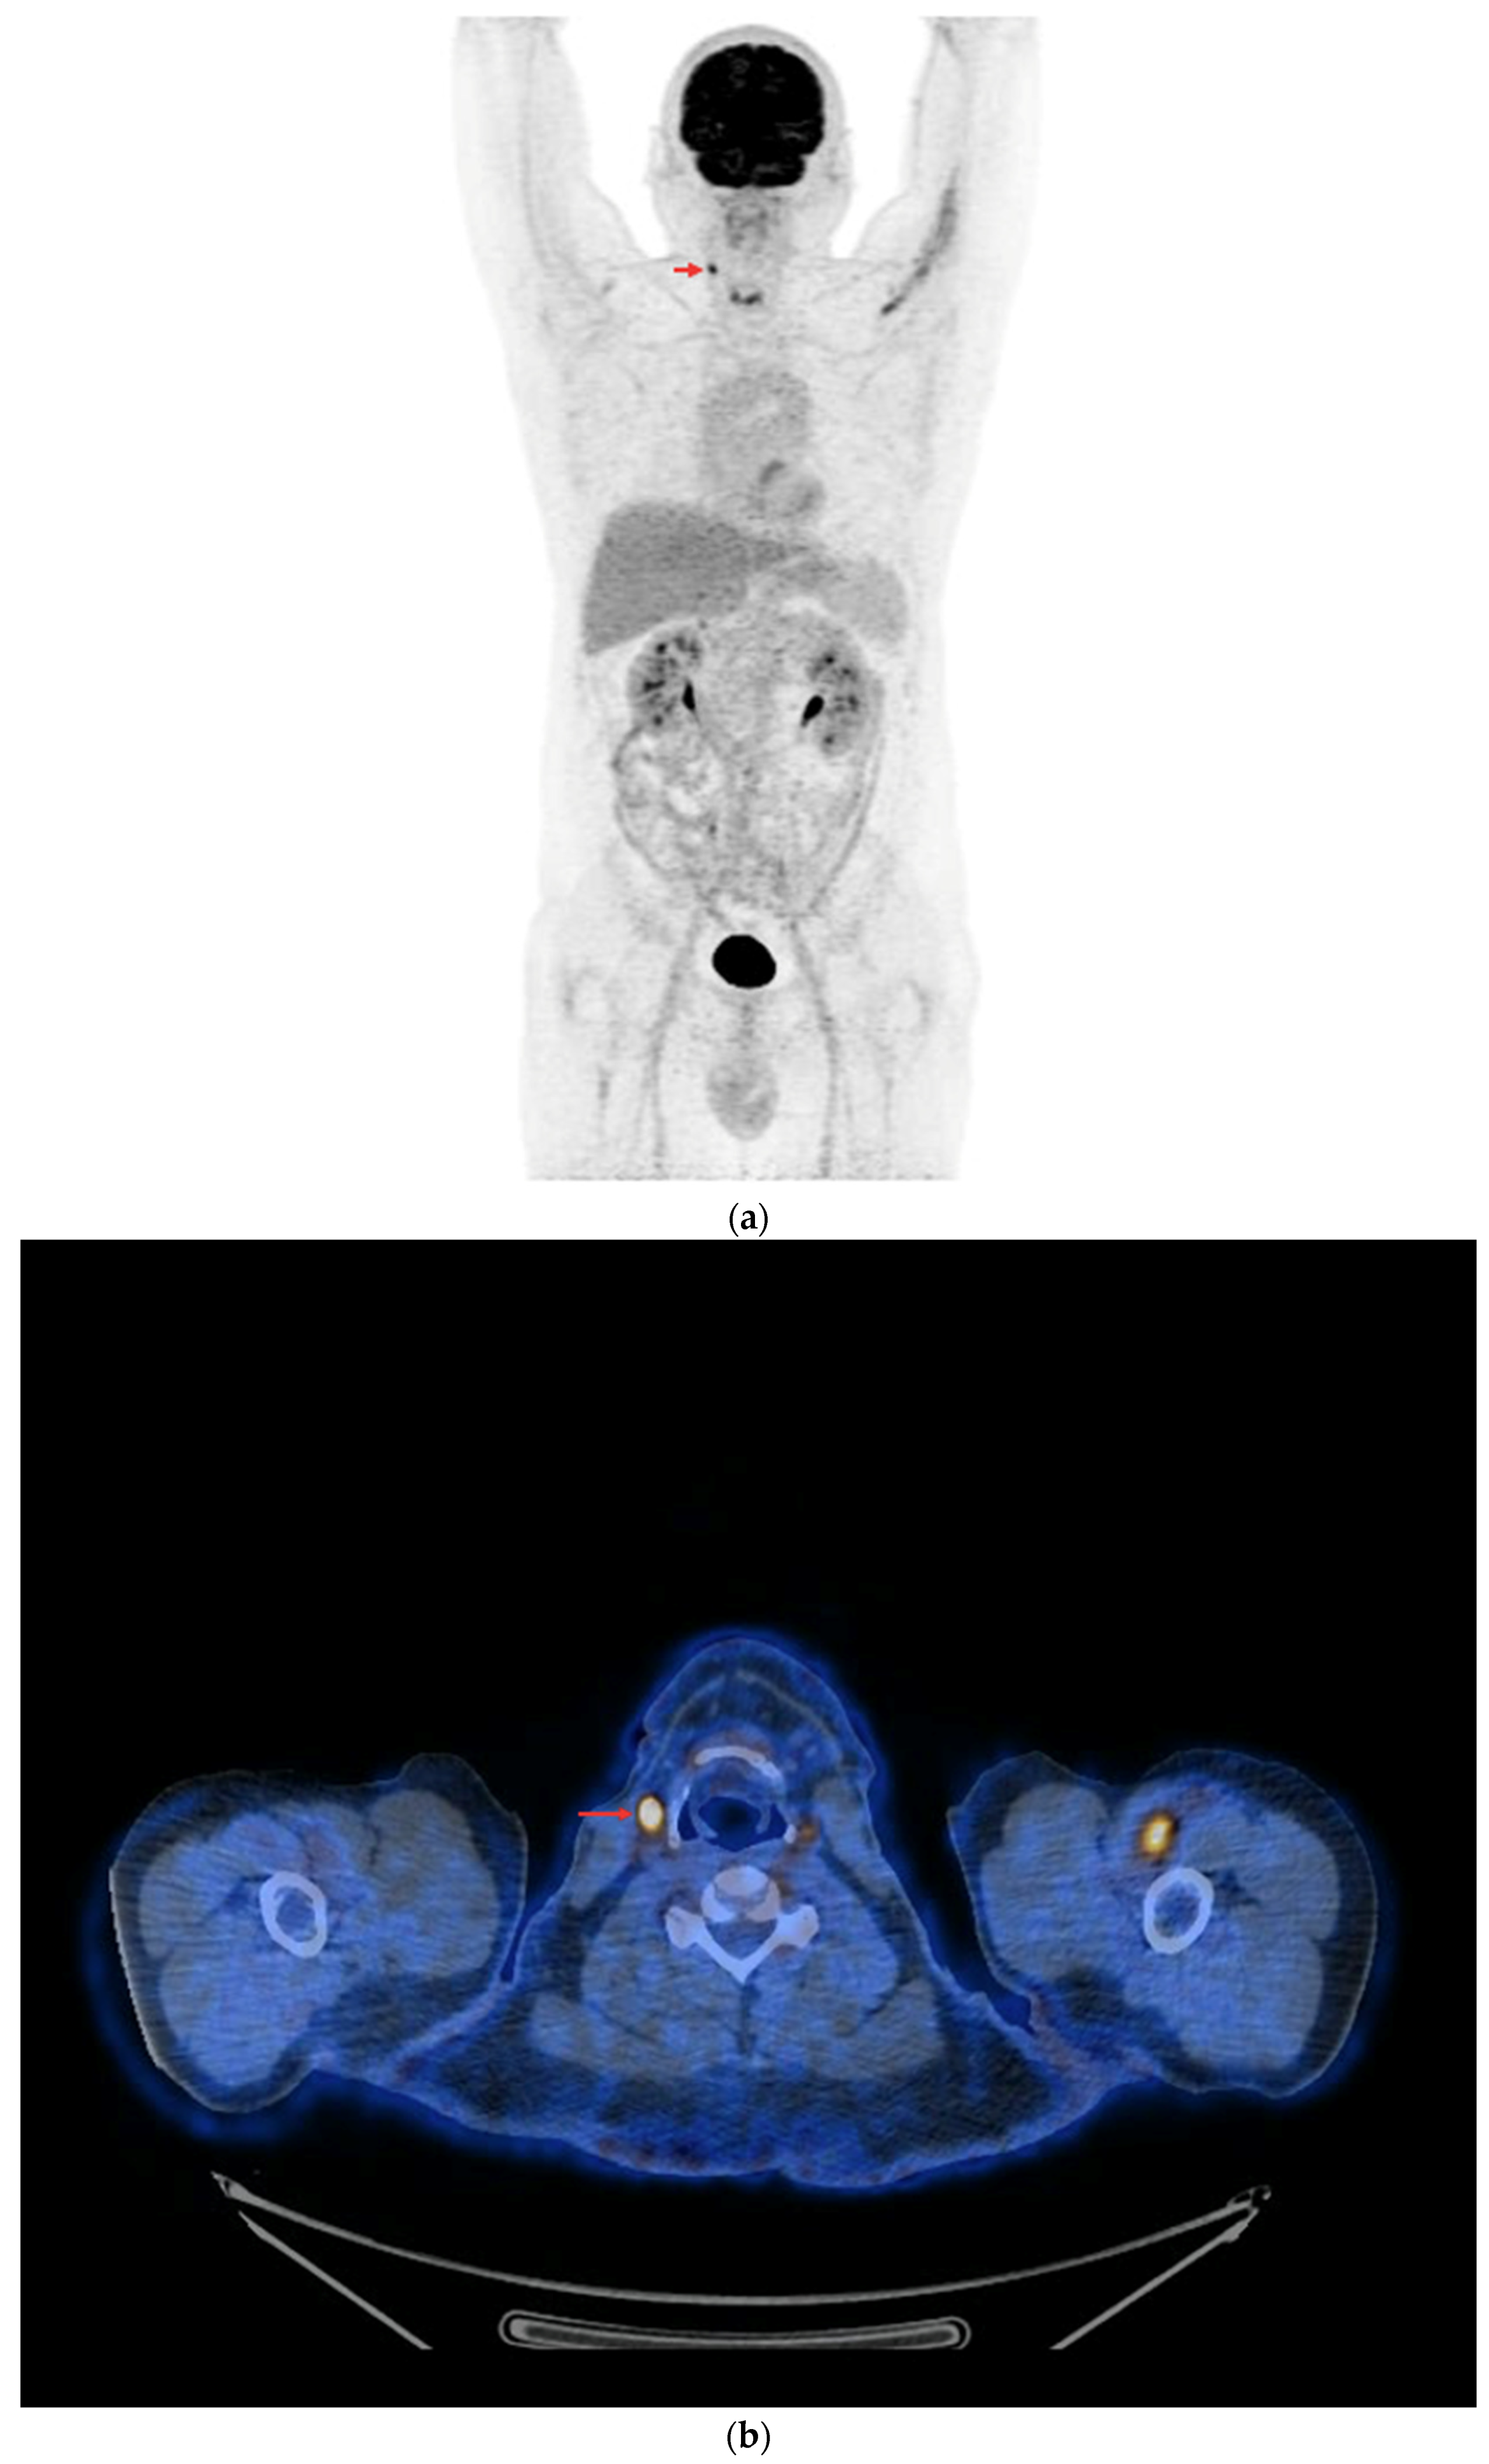

In the subgroup of 48 PET/CT examinations after rhTSH stimulation, in 18 (18/48—37.5%), positive results were obtained (Figure 8a,b). The other 30 studies in this subgroup (30/48—62.5%) were assessed as negative, and no foci of increased [18F]FDG accumulation associated with DTC were found. The difference in the number of positive results in each subgroup was not statistically significant (p = 0.83).

Figure 8.

PET/CT with [18F]FDG with rhTSH stimulation (a) Maximum-intensity projection (MIP). (b) Axial fusion projection. These show an example of accumulation of the [18F]FDG in the right cervical lymph node (red arrow).